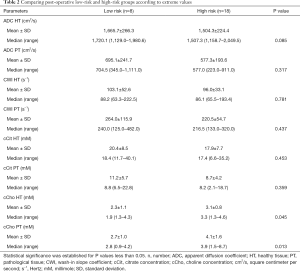

Topographic MRI data from the post-operative LR (n=8) and HR (n=18) patient groups showed a high proportion of T3 MRI findings (77.8% vs. 37.5%) in HR patients (Tables 1,2).

Full table

The mean abnormal ADC values were markedly lower in the HR group than in the LR group, although the difference was not statistically significant (P=0.06). However, cCho mean values were significantly higher among HR patients (3.6 vs. 2.2; P=0.001).